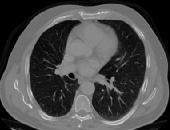

4.1.5 Chest CT

Chest CT scans play a relevant role in diagnosing a wide range of thoracic diseases, from infections to malignancies. By analyzing those scans, it is possible to detect diseases in the chest region, including pneumonia and cancer. The selected chest CT dataset 555https://www.kaggle.com/datasets/mohamedhanyyy/chest-ctscan-images contains 967 images across normal and three cancer types: adenocarcinoma, large-cell carcinoma, and squamous-cell carcinoma. Figure 6 provides a visual representation of the four highlighted classes.

Table 1 provides a detailed summary of the datasets used in this study, highlighting the total number of images in each dataset, the distribution between training and testing sets, and the specific classes represented. Each dataset corresponds to a particular medical imaging domain with distinct classes relevant to diagnosing specific conditions. Also, Fig. 9 presents a representative image from each dataset, allowing for a visual comparison of the diverse tones, patterns, and textures present across the datasets. Such diversity in visual characteristics highlights the need for a robust model that can handle all image characteristics.